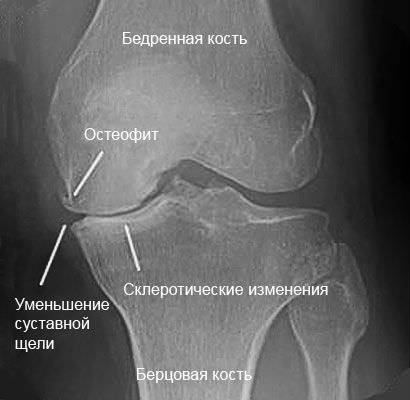

- Одной из самых важных процедур при подагрических симптомах является рентгенологическое исследование. Благодаря ему становится ясна вся картина болезни суставов. Рентген пораженного подагрическим артритом сустава помогает определить наличие в сочленении патологических изменений, которые вызваны образованиями из кристаллов солей. В случае подагры хронического характера на снимке будут хорошо заметны светлые пятна, указывающие на места поражения.

- Артрит 1 степени коленного сустава. Основные его проявления – боль в колене после физических нагрузок. Колено перестает болеть после отдыха. С утра может наблюдаться скованность сустава, но она быстро проходит. На этой стадии деформационные процессы еще не развились, но на рентген-снимке видны костные разрастания, нарушено кровоснабжение хряща. В большинстве случаев достаточно симптоматической терапии.

- Артрит 3 степени коленного сустава. Это последняя стадия, поэтому высока вероятность осложнений. Болезнь прогрессирует, поэтому хрящ и кости деформируются, атрофируются мышцы, хрящевая ткань заменяется остеофитами. Боль не покидает пациента даже в ночное время. Колено может болеть на перемену погоды. На рентген-снимке видно сужение или отсутствие суставной щели.

Остеофит и склеротические изменения коленного сустава